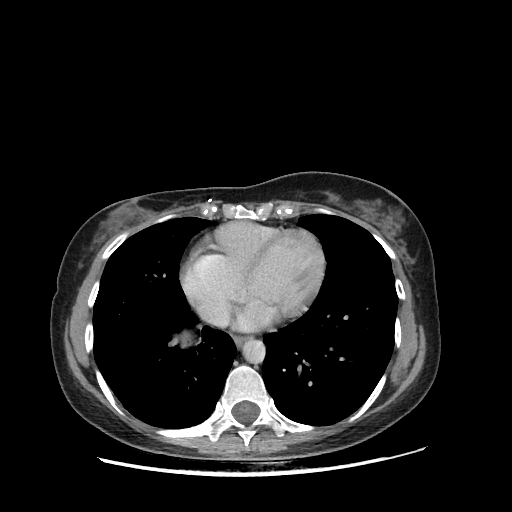

Image Grid

4Γ—3 grid: Rows show different image types (Original NATIVE, Reconstructed NATIVE, Original VENOUS, Generated VENOUS), Columns show windowing techniques (No Window, Lung Window, Mediastinum Window)

Original VENOUS CT scan

Full window (WL 1023.5, WW 4095 β†’ Low βˆ’1024, High +3071)